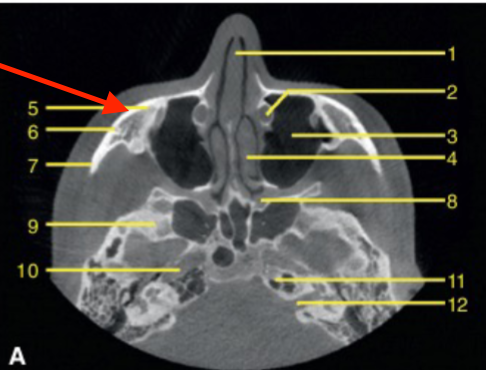

axial

what plane is this

level of maxilla (above maxillary teeth)

at what level is this

mandibular condyle

what structure is this

coronoid process

maxilla

which arch is this

pterygoid process

identify the structure

mandible

mandibular foramen

identify structure

apical of roots

genial tubercule